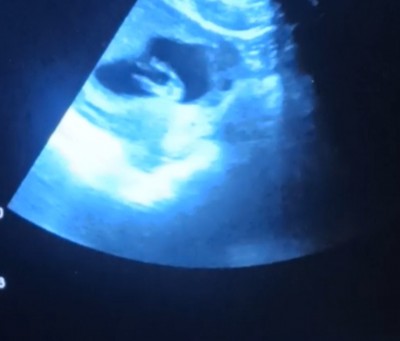

Tecrübeli anneler sizce kızımı oglummu heyecanlıyım da

Kızlar merak ediyorum sizce ufagımın cinsiyeti

Gebelik haftası

13 haftalık gebelik

Cinsiyetini söylemedimi doktor cnm bana erkek gibi geldi salıkla al kucagina

Canım kız gibi dedi